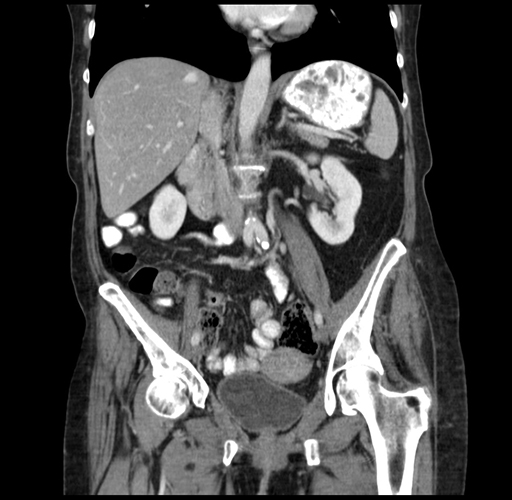

Coronal Venous